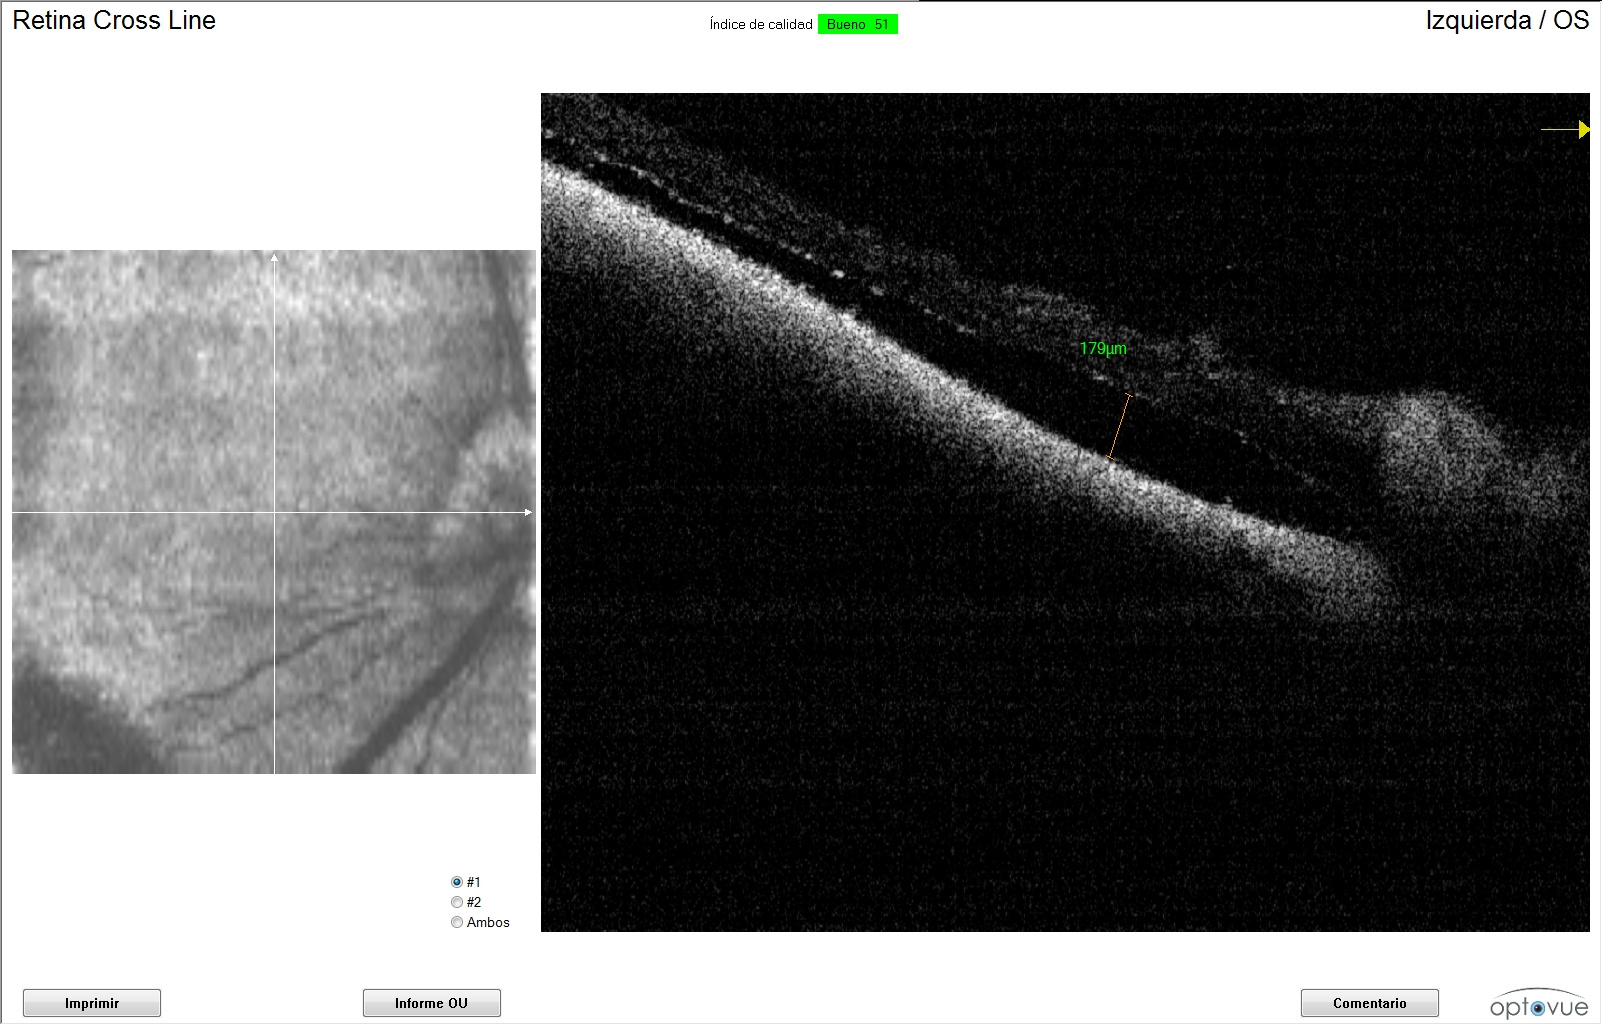

De cada una de la imágenes de OCT se midió la distancia entre la neuroretina y el epitelio pigmentado de la retina (EPR). Evaluando de esta manera, la evolución y respuesta al tratamiento del desprendimiento de retina exudativo. Se cápturaron imágenes de la zona tapetal, no tapetal y región peripapilar.

Se obtuvieron imágenes de OCT donde progresivamente se ha disminuido la distancia entre la neuroretina y el EPR, apreciando de esta manera una reducción progresiva del exudado inflamatorio.Fueron analizadas todas las capturas de la zona peripapilar.

La primera medición que obtuvimos del ojo derecho mediante la OCT fue de 363 μm. Las siguiente mediciones en cada seguimiento fueron de 235, 80, 67 y 34 μm. Respecto al ojo izquierdo se obtuvo una primera medición de la separación de la neuroretina del EPR de 645 micras. Con valores de 363, 179, 28 y 0 μm en la siguientes revisiones.

La recuperación de la respuesta de amenaza y reflejos pupilares normales fueron a partir de la quinta revisión, llevando en ese momento 42 días de tratamiento, manteniéndose hasta la actualidad con una buena función visual recuperando sus hábitos y costumbres habituales.